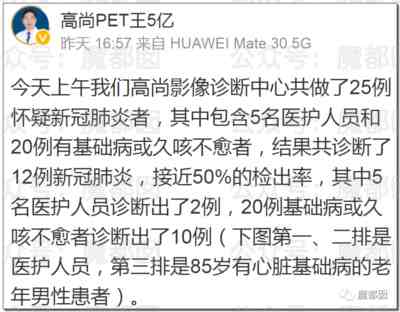

这个我们在过去几天的文章中写过多次,我们好像是所有公众号里最早写这波肺炎的,今天再给大家一个案例,这批肺炎总量还真的不小:

第六、现在医护真的有那么忙吗?是真的!

我们已经贴了不知道多少了,现在最苦最累的就是医护们,拼死拼活的抢救,所以请大家多给他们一点容忍和理解!